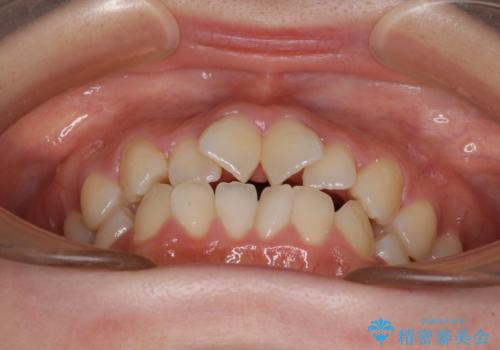

- 前歯のデコボコと非接触の上下前歯を気にして来院された患者様です。

上下前歯の隙間は舌の突出癖によるもので、隙間改善のためには舌のトレーニングがとても重要となります。

口元の突出感はないため、抜歯矯正の適用ではありませんが、デコボコを解消する際に外側に拡大されてしまうと治療前と比べて出っ歯になった印象にもなるため、舌の突出癖の改善が必須となります。